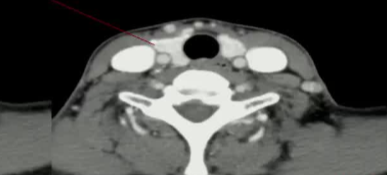

病例,44F 主动监测(wait and see)2年后,要求做甲状腺微创治疗。两次献血穿刺,一次发现包膜侵犯,确定外科治疗

![]() |